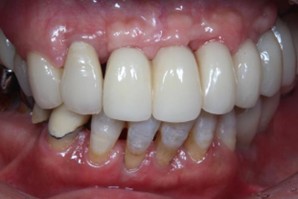

40代 女性

- リスク・副作用

- 術後疼痛、歯肉腫脹

- 治療の費用

- 合計¥686,000(税込)

【内訳】

インプラント(1本) ¥440,000

その他費用¥246,000

(薬・注射・レントゲン・CT・データ分析・骨造成・サージカルステント・血液検査) - 年齢/性別

- 40代/女性

- 患者の具体的な症状

- 左上6欠損のため義歯を使用していたが、噛むと痛みがあり不快なため、インプラント治療を希望

- 検査方法

- コーンビームCT、レントゲン撮影

- 診断結果

- 左下6欠損

- 治療詳細

- コーンビームCTによる画像診断で垂直的な骨高が不足し骨密度が少ないため、ソケットリフトによる骨再生治療とインプラント埋入を同時に行った。

- 通院回数

- 7回

- 治療期間

- 7か月